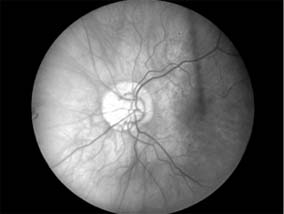

Papillitis needs to be differentiated from pap-illedema (Figure 14-9). In papilledema there is often greater elevation of the optic nerve head, nearly normal visual acuity, normal pupillary response to light, associated intracranial pressure, and an intact visual field except for an enlarged blind spot. If there has been acute papilledema with vascular decompensation (ie, hemorrhages and cotton-wool spots) or chronic papilledema with secondary ischemia of the optic nerve, visual field defects can include nasal nerve fiber bundle defects and nasal quadrantanopias. Papilledema is usually bilateral, whereas papillitis is usually unilateral. Despite these obvious differences, differential diagnosis can be difficult because of the similarity of the ophthalmoscopic findings and because papilledema can be quite asymmetric and papillitis bilateral in some postviral events (eg, Devic's disease, or neuromyelitis optica; see below).

Figure 14-9

Figure 14-9: Mild papilledema. The disk margins are blurred superiorly and inferiorly by the thickened layer of nerve fibers entering the disk.